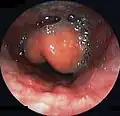

Diagnosis may be confirmed by direct inspection using a laryngoscope, although this may provoke airway spasm.[21] If epiglottitis is suspected, attempts to visualize the epiglottis using a tongue depressor are discouraged for this reason; therefore, diagnosis is made on basis of indirect fiberoptic laryngoscopy carried out in a controlled environment like an operating room.[21] An infected epiglottis appears swollen and is described as having a "cherry-red" appearance.[22] Imaging is rarely useful, and treatment should not be delayed for this test to be carried out.[21]

Swollen epiglottis in laryngoscopy -